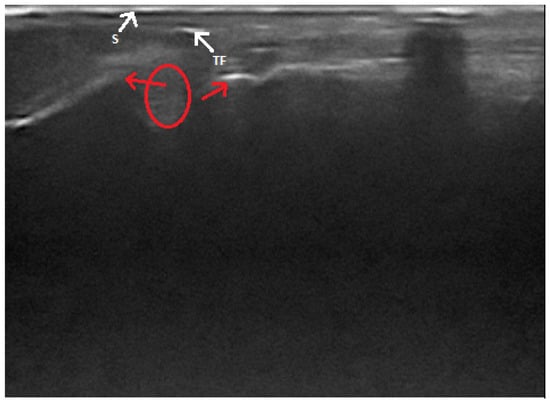

Figure 4. Ultrasonographic image of total Achilles tendon rupture. Ends of the torn tendon (red arrows), a hematoma (circle), a fragment of a tendon (TF) and the skin surface (S) is shown.

In the extant literature, there are some descriptions of ultrasound findings of total and partial Achilles tendon ruptures. The best visibility of the tendon can be achieved in the caudal–plantar acoustic window, in the longitudinal and transverse planes [43]. The complete rupture of a tendon appears as a break in the continuity of its fibrillar echostructure (Figure 4). The ends of a tendon are described as “drumstick-like” non-homogeneous structures with increased echogenicity, and they move relative to each other in a dynamic examination. Between them, there is often a hematoma, which appears as a heterogenous, irregularly delineated, more or less anechoic area, with hyperechoic particles inside of it [14,40]. If the rupture is close to the tendon attachment on the calcaneus, its surface is clearly visible. It is possible to visualize an avulsion fracture only if the separated bone fragment is larger than 3 mm [14]. In the case of a partial rupture of the Achilles tendon, the intact part shows its typical appearance, with its fibrillar structure partially preserved. Damaged parts of the tendon lose their normal echogenicity and this area is heterogeneous, hypoechoic-to-anechoic, and irregularly delineated. Sometimes, a thin layer of anechoic fluid can be seen between the tendon and its sheath [14,40]. According to some authors, it is impossible to distinguish between a complete and partial rupture of a tendon [46]. Based on changes in the common calcaneal tendon’s size and echogenicity, ultrasonography may also be useful in monitoring its healing process. However, an ultrasound is unable to determine the exact age of the injury and the time until it might be healed [40].